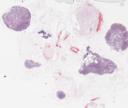

41-33a: Amöbiasis (Amöbiom) (HE)

41-33b: Amöbiasis (Amöbiom) (PAS)